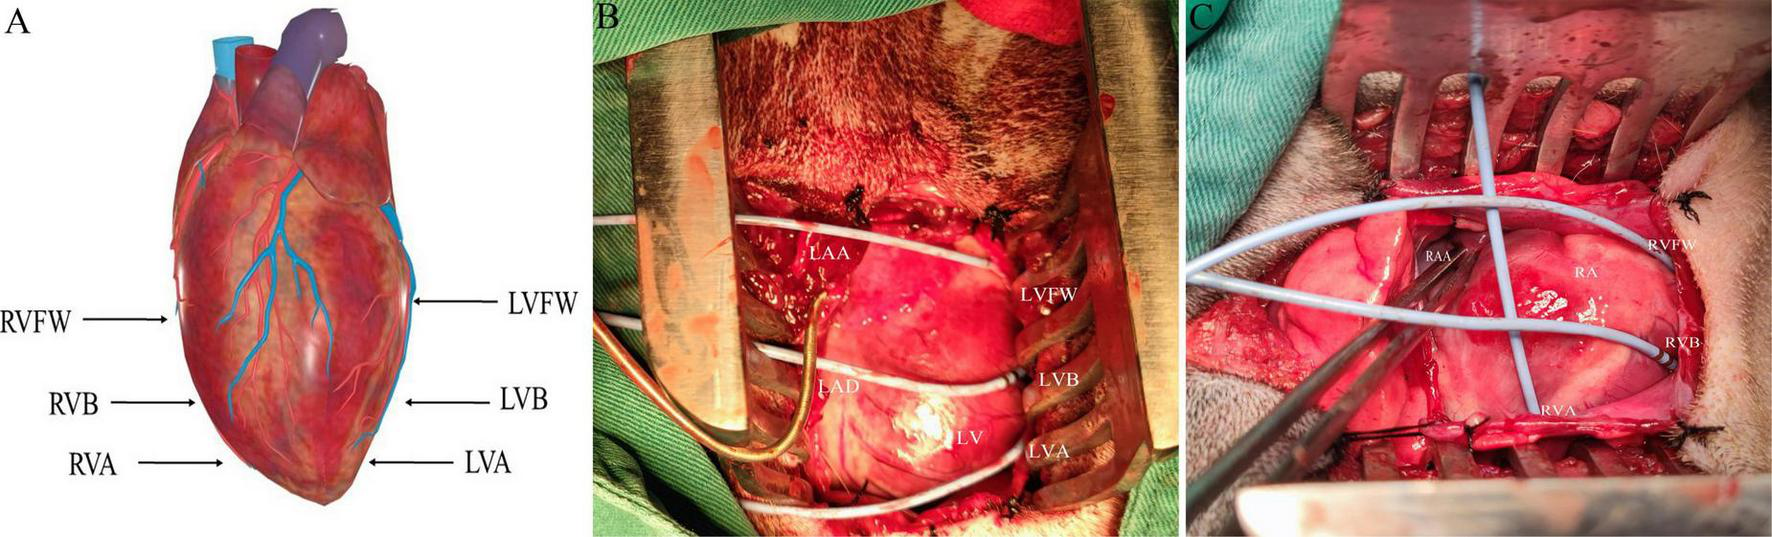

The electrophysiological testing was performed before and after MNS. Effective refractory period (ERP) in the right ventricular epicardium at the apex (RVA), free wall (RVFW), and base (RVB) and left ventricular epicardium at the apex (LVA), free wall (LVFW), and base (LVB) were evaluated during ventricular pacing at 300 ms cycle lengths (CLs) using stimuli at twice threshold. Figure 3 shows the schematic diagram of electrode placement position during electrophysiological testing. After every eighth drive stimulus (S1), a premature extra stimulus (S2) was introduced. As the S1–S2 intervals approached the ERP, decrements were reduced to 2 ms. ERP was the most prolonged S1–S2 interval at which S2 failed to capture. ERP dispersion was the maximum difference among all sites tested.

FIGURE 3

The schematic diagram of electrode placement position during electrophysiological testing (A). (B,C) Are electrodes placed in the left ventricle and right ventricle, respectively. LVFW, left ventricular free wall; LVB, left ventricular base; LVA, left ventricular apex; LAA, left atrial appendage; RVFW, right ventricular free wall; RVB, right ventricular base; RVA, right ventricular apex; RAA, right atrial appendage.